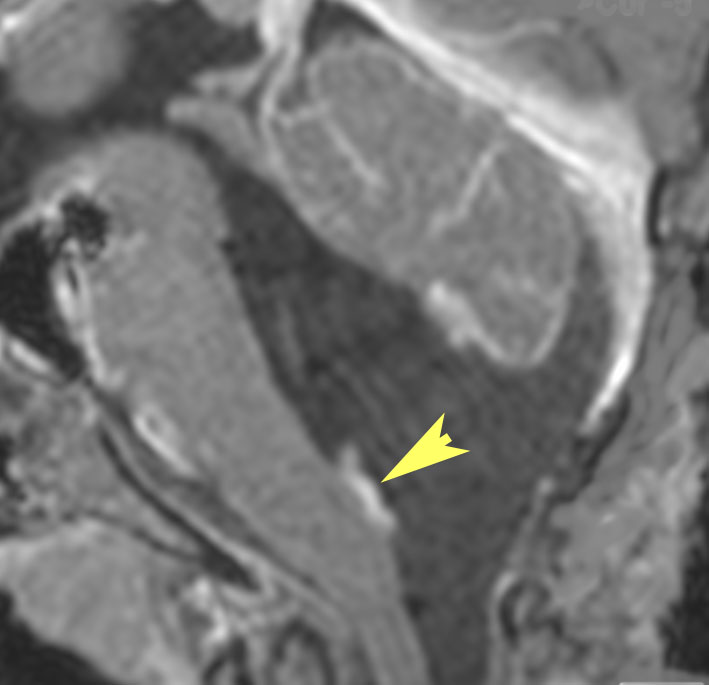

小脳毛様細胞性星細胞腫のFLAIR画像所見

壁在結節を伴うのう胞性小脳毛様細胞性星細胞腫は,結節を手術摘出すれば治癒するものです。しかし,あたかも腫瘍が残っているようなMRI画像所見が残ることがあります。

この例は,10歳の子どもに無症状で偶然発見された大きなのう胞性小脳毛様細胞性星細胞腫です。開頭手術で腫瘍結節は全摘出して腫瘍のう胞は縮小したままです。(画像はクリックすると拡大して見えます)

開頭手術で白く増強される結節部分だけを摘出しました。MIB-1はやや高値で3%と報告されました。病理組織診断は,WHO grade 1 毛様細胞性星細胞腫です。

6年後のMRI FLAIR画像です。摘出腔周囲の高信号域が残存しています。ここまで残ると腫瘍周辺浮腫ではありませんし,腫瘍細胞が左小脳半球に広範囲に浸潤して残存しているものだと判断されます。しかし,6年間で病変の増大傾向がありませんでした。この残存腫瘍(らしい所見)に対して放射線治療や化学療法を行うべきかどうか,結論は出ていません。しかし,経過観察を続けても増大して来ない例があることは確かです。一方で,この高信号領域が拡大したり,ガドリニウム増強される病変が再出現して治療がまた必用となることもあります。